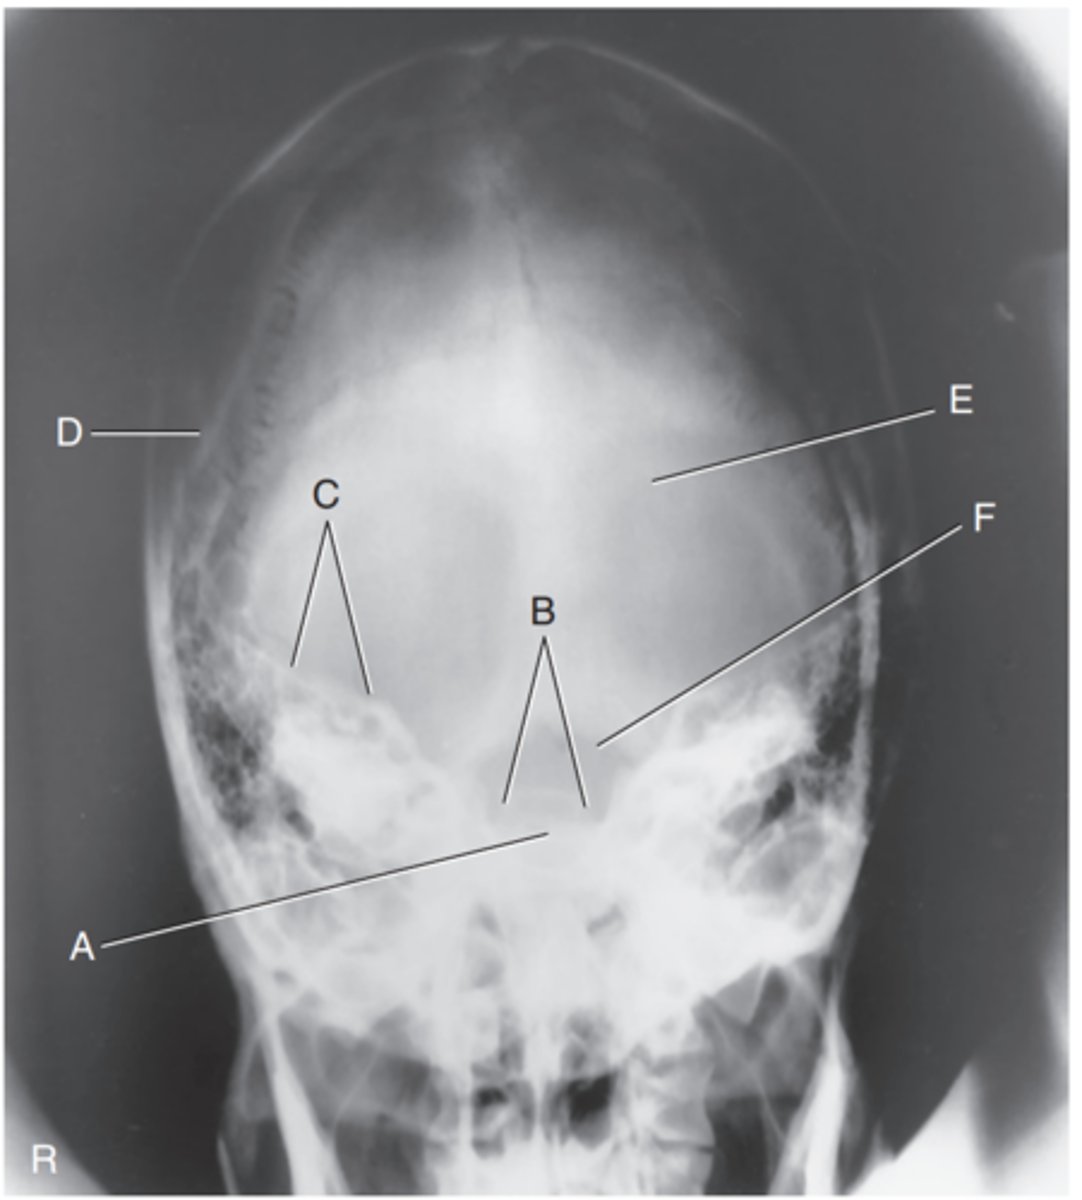

EAM

Label A

Mastoid portion of temporal bone

Label B

Occipital bone

Label C

Lambdoidal suture

Label D

Clivus

Label E

Dorsum sellae

Label F

Posterior clinoid processes

Label G

Anterior clinoid processes

Label H

Vertex of cranium

Label I

Coronal suture

Label J

Frontal bone

Label K

Orbital plates

label L

Cribriform plate

Label M

Sella turcica

Label N

Body of sphenoid (sphenoid sinus)

Label O

Petrous portion of temporal bone

Label P